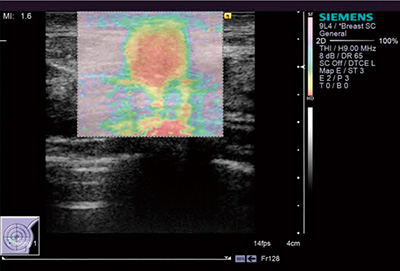

■Virtual Touch Imaging(VTI)

ARFIの作用で生じる微小な組織変位量を測ることによって,組織の相対的な硬さのイメージングを得ることができる。硬い組織は変位量が少なく,軟らかい組織はそれが大きいことを利用する。これは,従来の用手的圧迫によるエラストグラフィと同じくストレインエラストグラフィの一種であるが,音響的作用を利用するためプローブをまったく動かす必要はなく,操作者の手技に依存するところが少ないのが特長である(図1)。

図1 VTIによる組織弾性イメージ:ARFI Imaging(乳頭腺管癌)

(画像ご提供:聖マリアンナ医科大学病院臨床検査部・桜井正児先生)